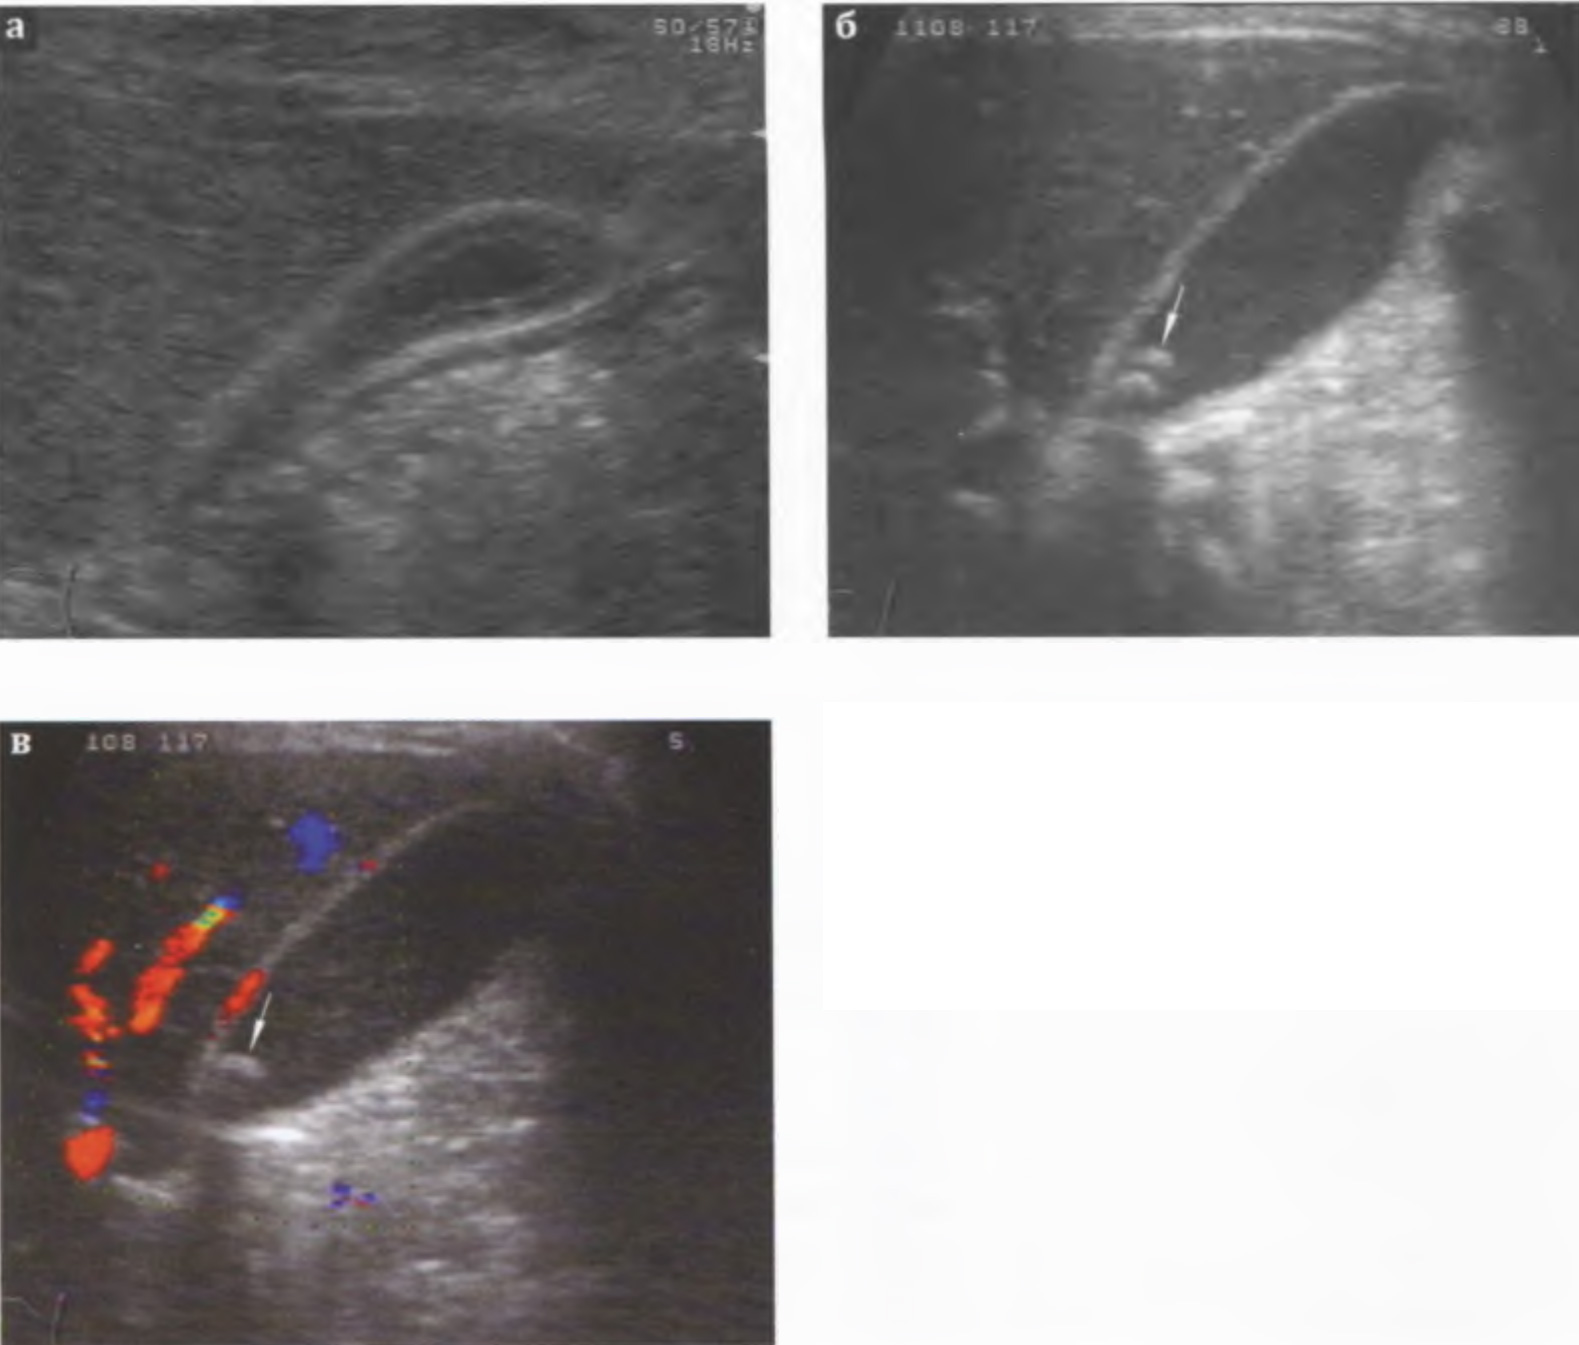

Острый холецистит сопровождается увеличением (диаметр > 3,0 см, длина > 8,0 см), реже - уменьшением размеров желчного пузыря, утолщением стенки > 0,4 см, изменением ее эхогенности (вначале она повышается, в дальнейшем - понижается), появлением слоистости стенки, усилением ее васкуляризации (рис. 3.5 а,б,в). В дальнейшем появляется нечеткость контуров. Содержимое желчного пузыря становится неоднородным: появляется эхогенная взвесь, сгустки, пузырьки газа. Часто определяются конкременты.

Рис. 3.6 а,б. Острый калькулезный холецистит, катаральная форма: умеренное утолщение стенки желчного пузыря.